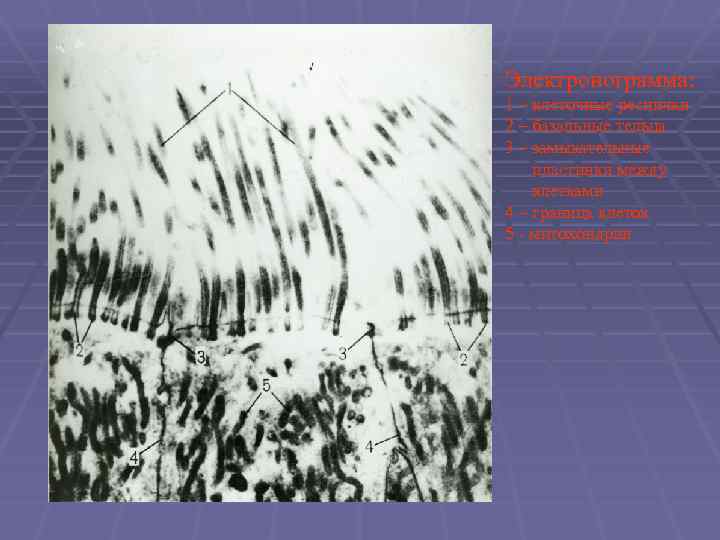

Электронограмма: 1 – клеточные реснички 2 – базальные тельца 3 – замыкательные пластинки между клетками 4 – граница клеток 5 - митохондрии